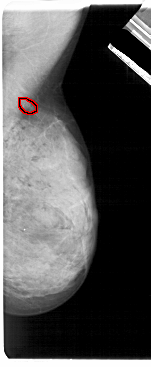

A_1874_1.RIGHT_MLO

RIGHT_MLO LINES 5491 PIXELS_PER_LINE 2251 BITS_PER_PIXEL 12 RESOLUTION 43.5 OVERLAY

FILE: A_1874_1.RIGHT_MLO.OVERLAY

TOTAL_ABNORMALITIES 1

ABNORMALITY 1

LESION_TYPE CALCIFICATION TYPE PLEOMORPHIC-FINE_LINEAR_BRANCHING DISTRIBUTION CLUSTERED

ASSESSMENT 4

SUBTLETY 2

PATHOLOGY MALIGNANT

TOTAL_OUTLINES 1

BOUNDARY